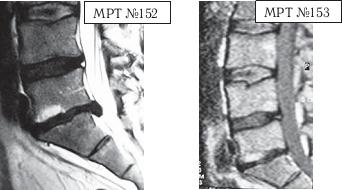

На МРТ № 152 наблюдается секвестрированная грыжа межпозвонкового диска в сегменте LV-SI. На МРТ № 153 наблюдается состояние поясничного отдела позвоночника после одного курса лечения методом вертеброревитологии. Многолетние наблюдения показали, что когда усилиями врача и пациента создаются идеальные условия для регенерации повреждённых дегенеративно-дистрофическим процессом межпозвонковых дисков и в период реабилитации с данным пациентом не происходят, например, случаи травматизации и «срывов», вследствие чрезмерной физической нагрузки, то выстраиваемая, благодаря методу вертеброревитологии, биомеханическая конструкция после последнего сеанса может держаться фактически год, — то есть весь продолжительный период постепенной регенерации вплоть до полной реституции межпозвонкового диска. Это подтверждено результатами МРТ-снимков, в том числе пациентов, живущих в дальнем зарубежье и не имеющих возможности по тем или иным причинам приезжать ко мне в клинику вертеброревитологии на контрольные сеансы. Однако контакт с пациентами не прерывается, что обеспечивает возможность отслеживать состояние их позвоночника в течение длительного периода времени. Приведу ещё пример, связанный с результатами лечения методом вертеброревитологии.